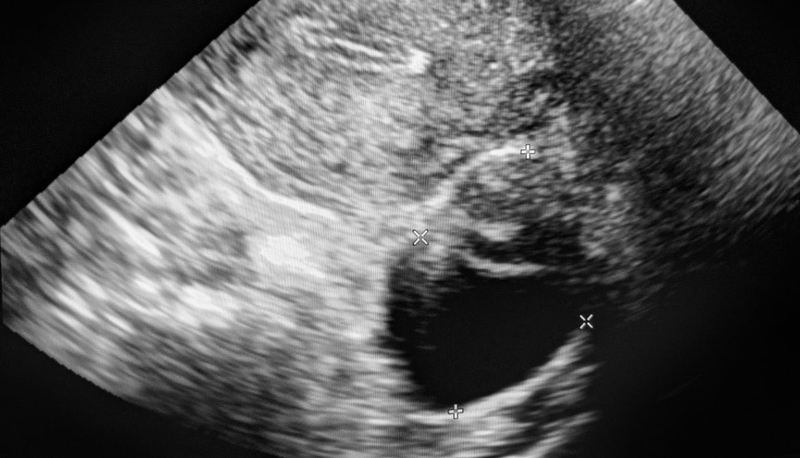

U nang và u xơ: Có gì khác biệt giữa hai loại u này 2

U nang và u xơ đều có thể được phát hiện qua siêu âm